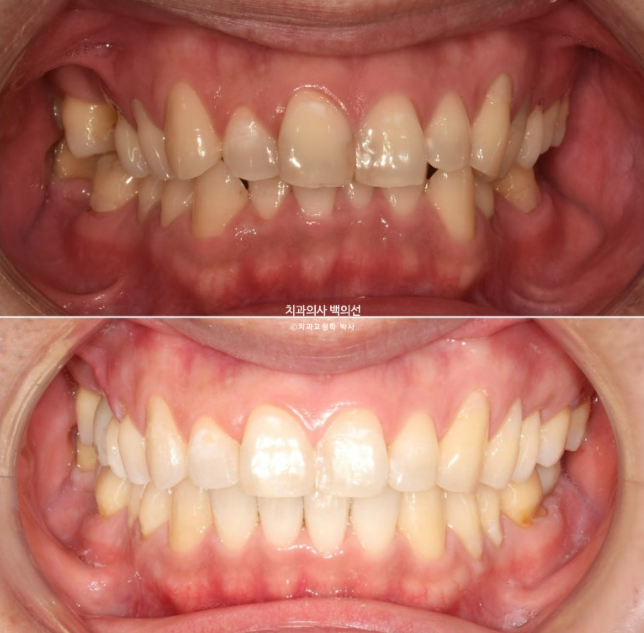

중심선 불일치와 심한 과개교합, 송곳니 덧니 등이 보입니다.

24.05~24.11

과개교합은 완벽히 개선이 되었고

이제 전 후 비교 보겠습니다.

교정치료 시간은 총 10개월 입니다.

환자분이 열심히 껴준다면 10개월 만에도 좋은 결과가 나옵니다.